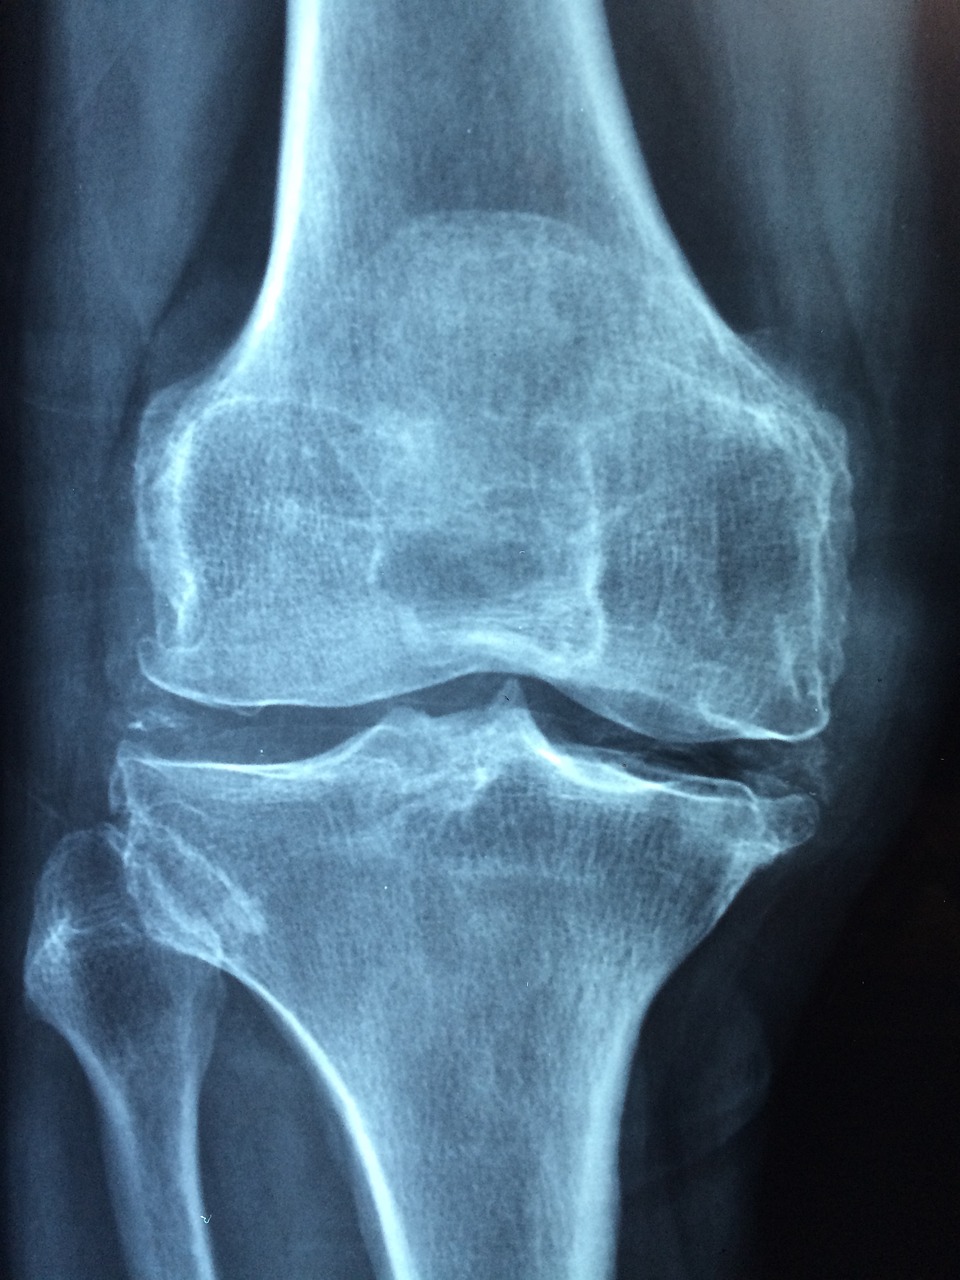

퇴행성 관절염이 진행되면 무릎이 O자형으로 변하고, X-ray 상에서 무릎 내측 연골이 닳아 뼈끼리 붙어 있는 모습을 확인할 수 있습니다. 이는 관절염 말기 상태로, 극심한 통증을 유발합니다.